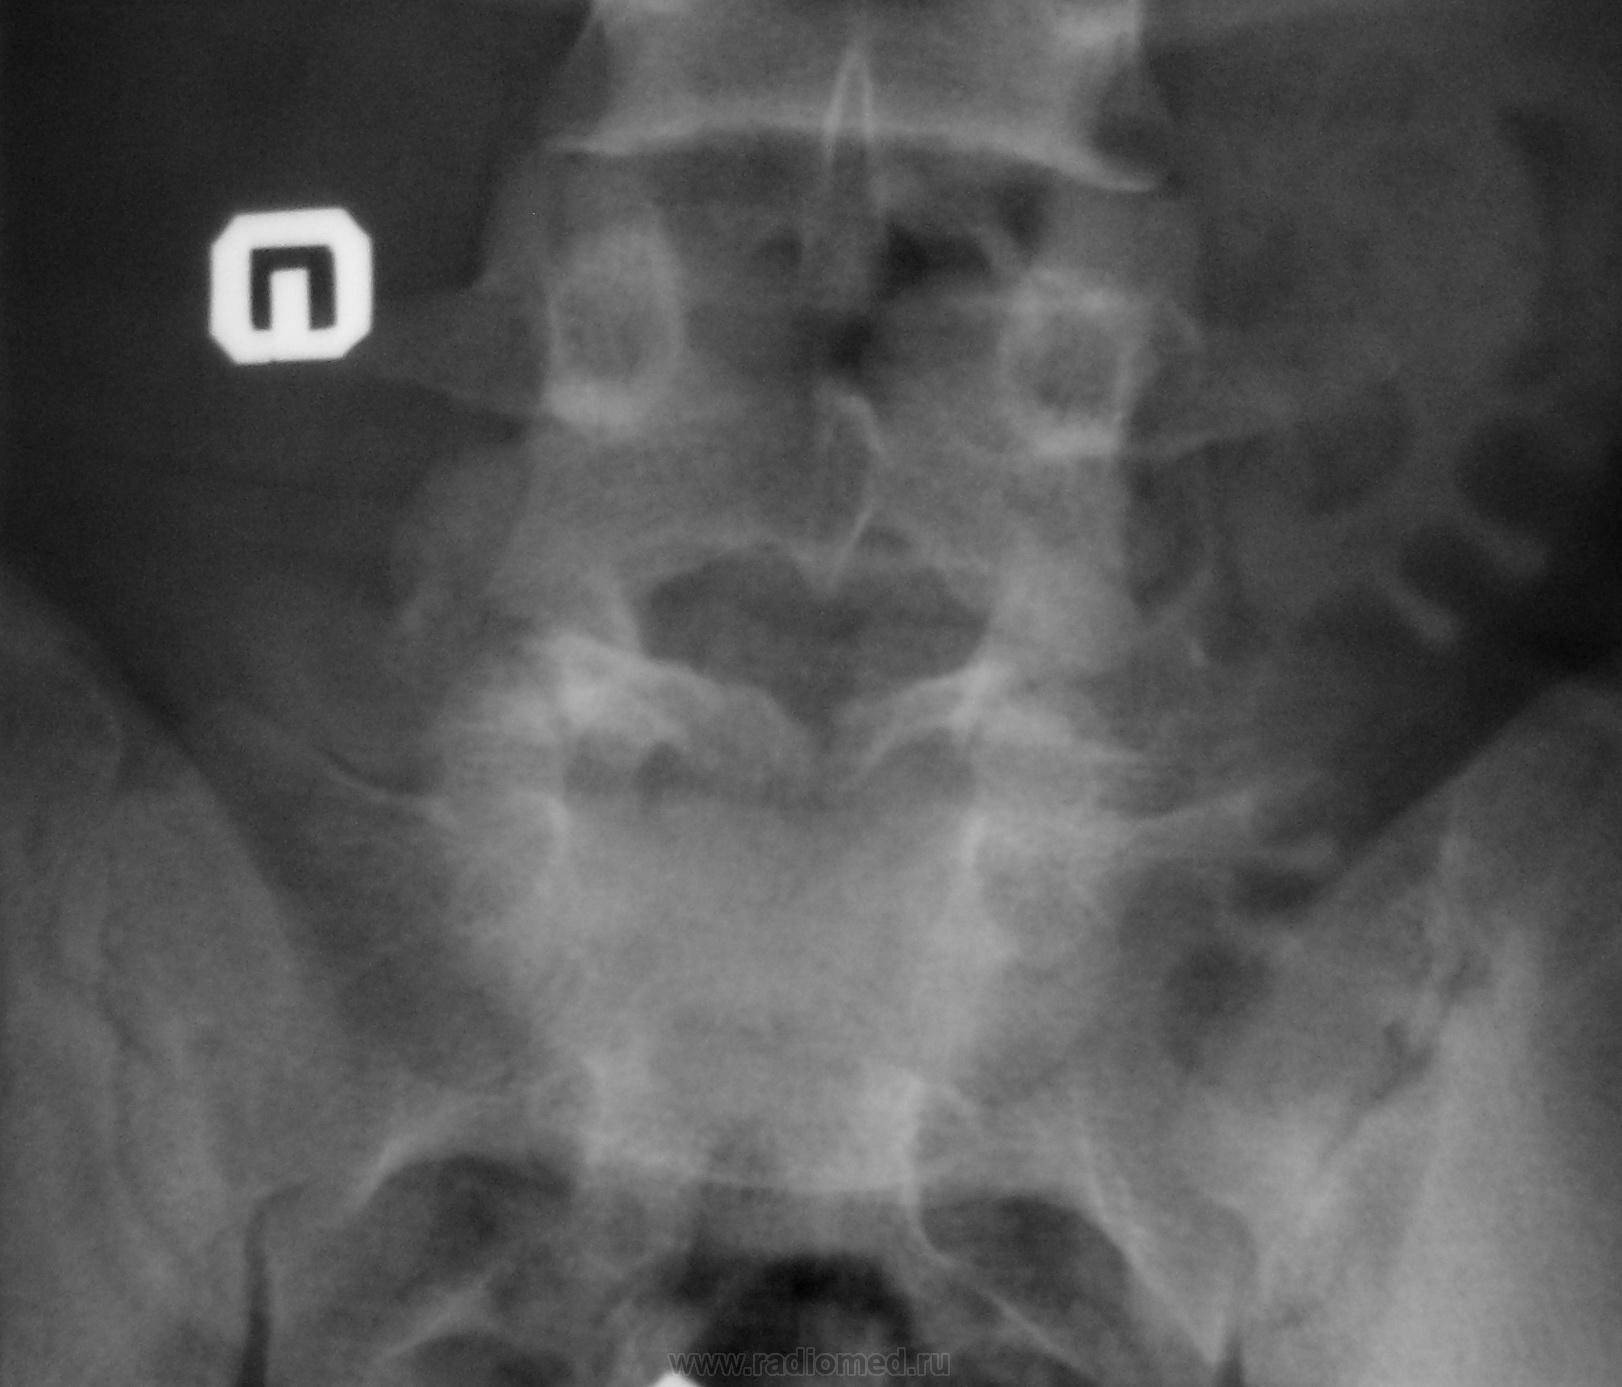

Молодой человек, занимаясь в спортзале, неаккуратно взял вес. Беспокоят боли в пояснице.

Истинный передний спондилолистез I степени и незаращение дужки L5

+1. Spina bifida S1.

На сколько я понимаю, при описании смещений в сегментах позвоночного столба принято оценивать смещение более краниального позвонка (как, например, при переломах оценивают смещение дистального отломка). С этой позиции, "Спондилолистез крестца кзади" звучит не совсем корректно.

На мой взгляд, сложно сказать явился ли листез следствием травмы (гипернагрузки), предыдущих снимков скорее всего нет. но исходя из умозаключения "где тонко, там и рвётся", смею предположить, что причина жалоб пациента находится именно на уровне спондилолистеза. ...правда, как облачить это в форму заключения протокола рентгенографического исследования я не знаю...

Если бы такой листез был следствием однократной гипернагрузки, думаю, что без инвалидной коляски бы не обошлось. Но о дальнейшем занятии таким спортом нужно задуматься.